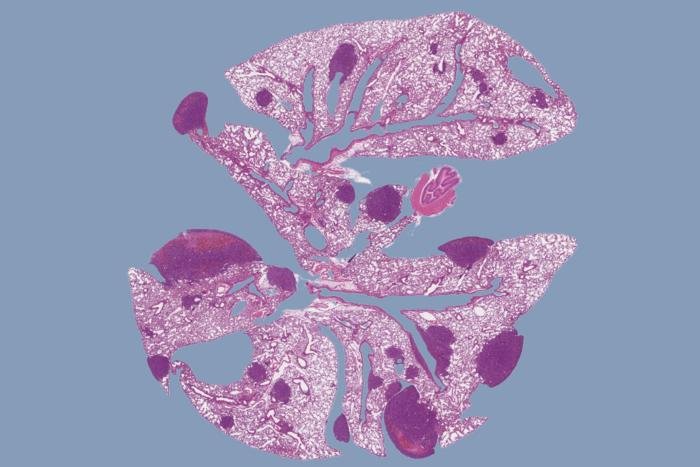

Elizabeth und Vincent Meyer Labor für Systemkrebsbiologie an der Rockefeller University